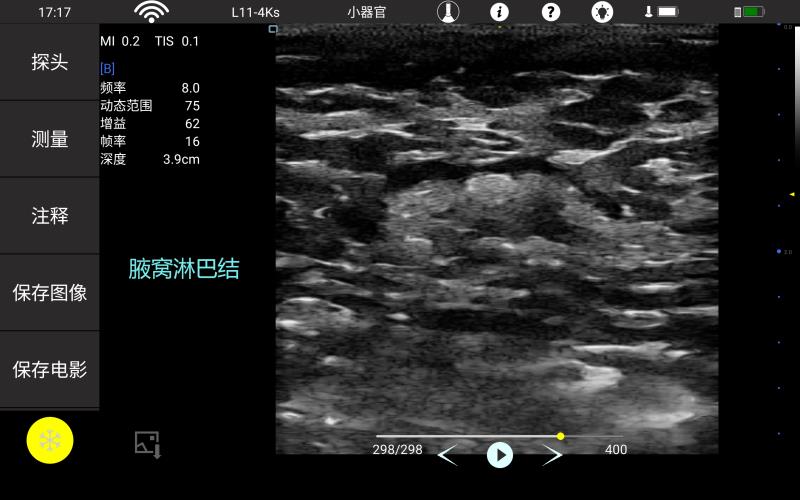

• 线阵

甲状腺

血管

神经

肌骨等